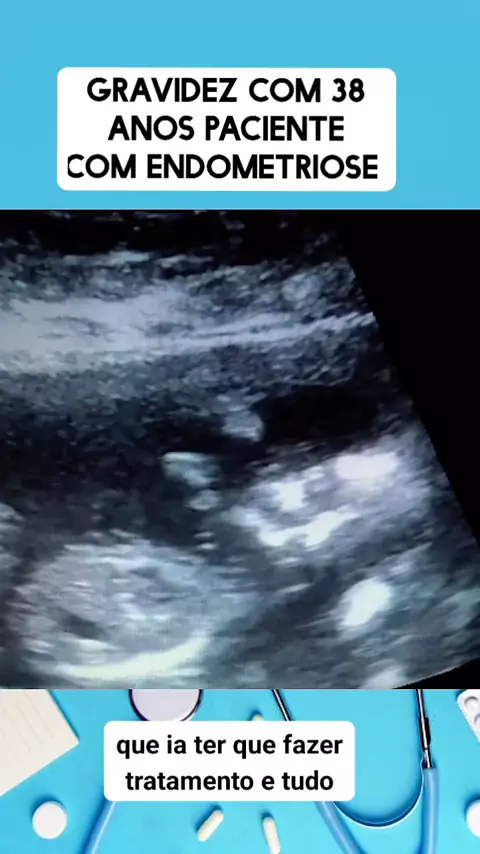

grávida com endometriose #medico #medicina #Saúde #viraliza